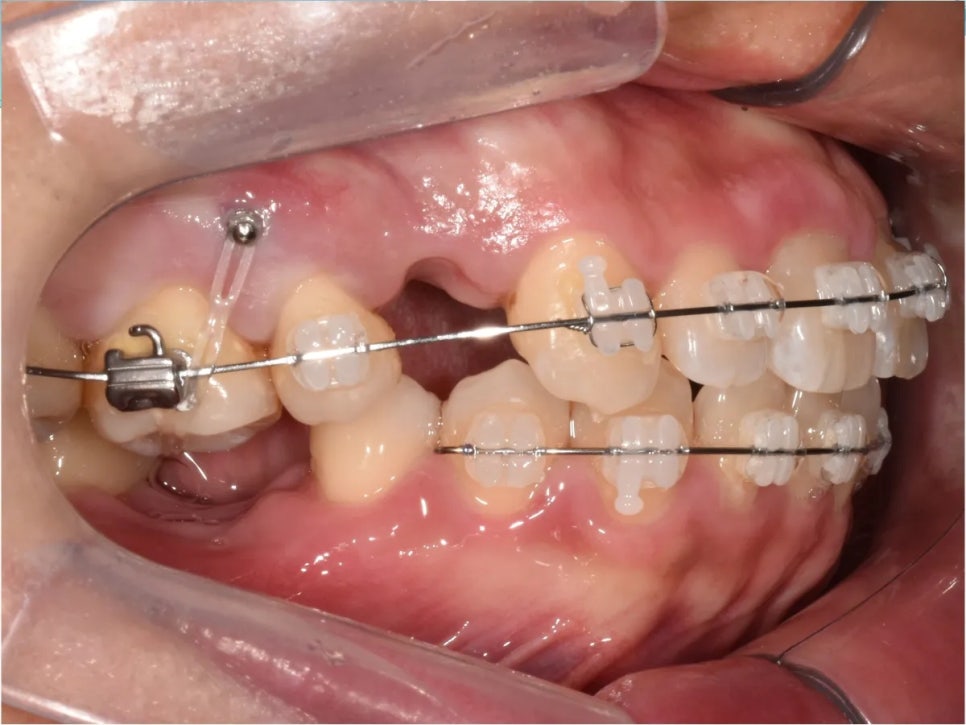

동시에, 정출되면서 바깥쪽(볼 쪽)으로 빠져나가 있던 어금니를 안쪽(입천장 쪽)으로 당기는 작업도 진행하였습니다. 어금니가 제자리에 정확히 위치해야 아래 치아와 정상적으로 맞물릴 수 있기 때문입니다.

정출되면서 바깥쪽으로 빠져나갔던 어금니를 안쪽으로 당겨주는 과정

이때 한 가지 세심한 처치가 필요했습니다. 어금니를 안쪽으로 움직이는 과정에서 아랫니와 간섭(부딪힘)이 생길 수 있기때문에, 반대쪽 치아에 '바이트 플레인(bite plane)'이라는 장치를 만들어주었습니다.

바이트 플레인이란?

치아 위에 붙이는 플라스틱 블록으로, 특정 치아끼리 닿지 않도록 교합 높이를 일시적으로 올려주는 장치입니다

반대쪽에 바이트 플레인을 만들어 일시적으로 끝까지 못 물게 해줘, 교합 간섭을 방지합니다